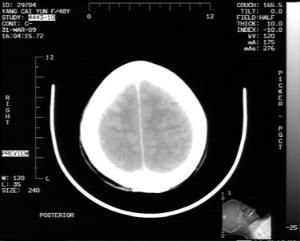

對擴管藥物的套用時間,應根據病人入院時的不同情況而定。如果腦缺血症狀較輕,無意識障礙及顱內壓增高的表現,CT掃描證實病灶較小,無梗塞後出血,起病後即可套用;而對中重度腦梗塞,入院時有意識障礙及顱內壓增高表現者,CT顯示腦梗塞面積大,占位效應明顯者,必須先行脫水治療,待病情穩定,症狀好轉方可套用,一般可掌握在發病2~3周。